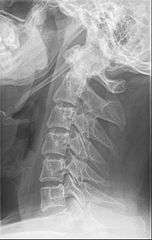

Radiograph, lateral view showing joint-like formation in ossified stylohyoid ligament